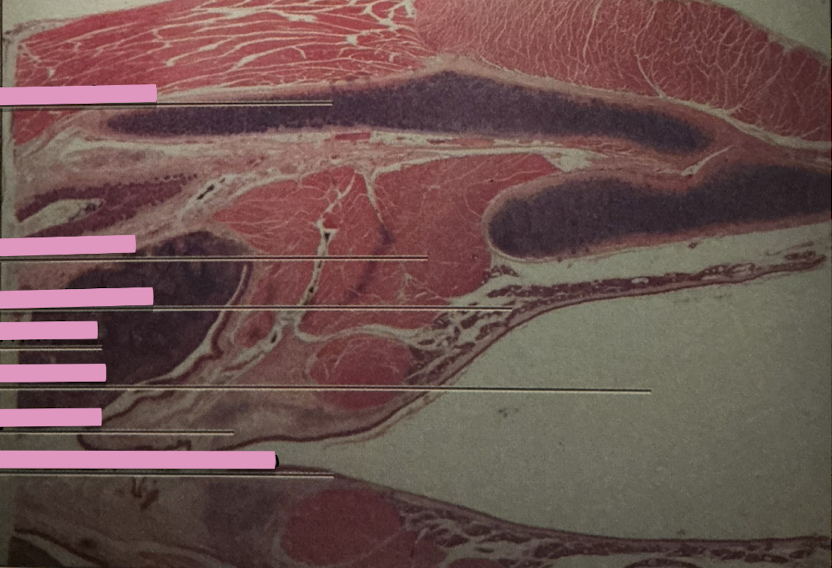

thymus

thymus

where does development of T cells occur?

Hassall’s Corpuscle

___________ sites accumulate dead T cells & involved in development of reg. T cells

spleen

spleen

macrophages. lymphocytes, entrapment/destroy old RBCs and platelets

hodgkin’s granuloma

hodgkin’s granuloma

cancer of lymph system - breakdown of red and white pulp

reed-sternberg cells

derived from B lymphocytes